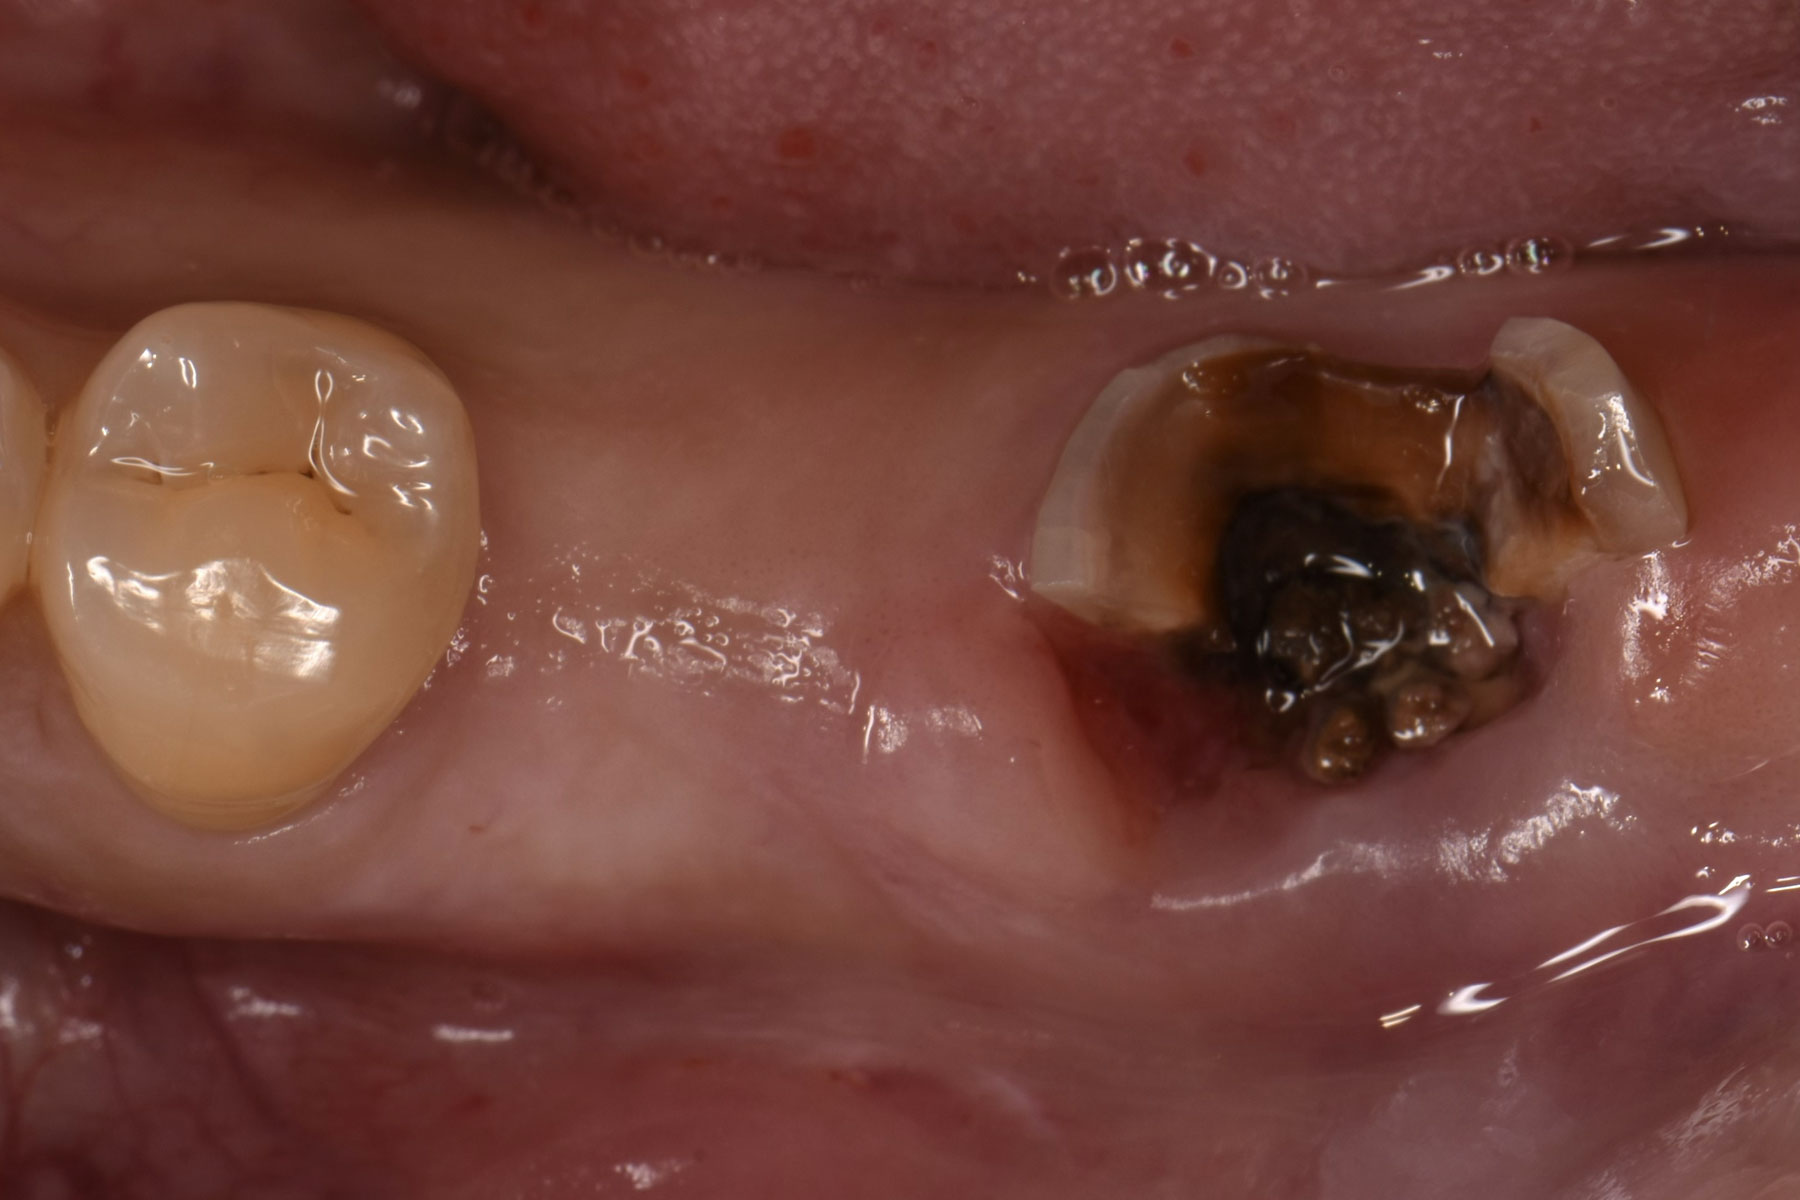

治療前

| 主訴 | 前歯が割れているため抜かなければいけないと言われた |